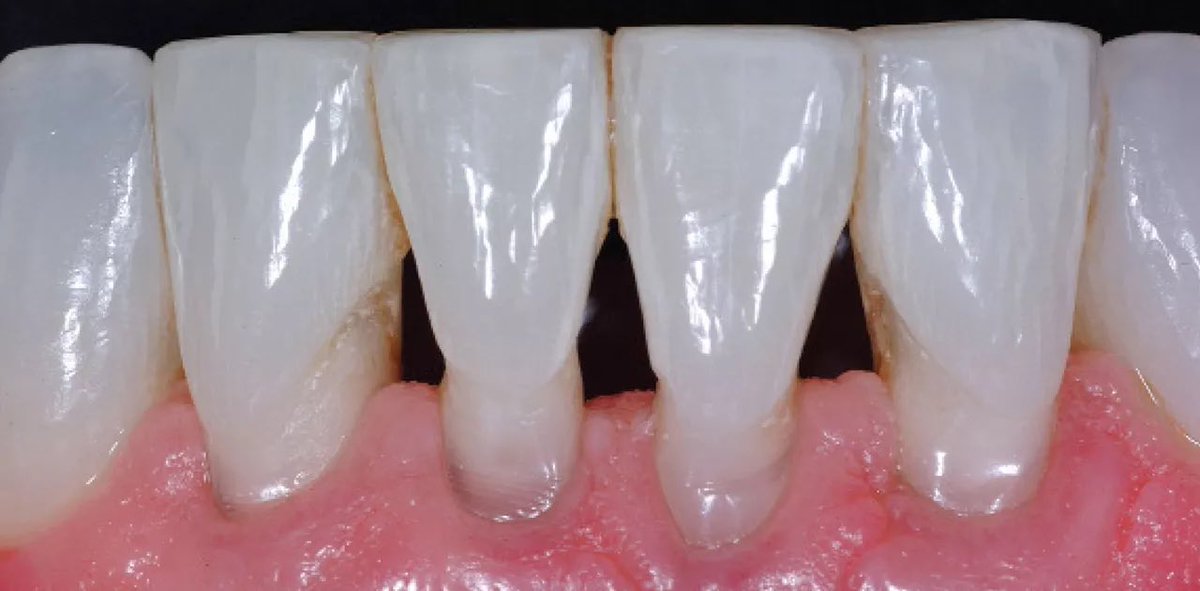

نسيت أن أذكر ، حاول ماتستخدم عود الأسنان لأنه أكثر شي يؤذي اللثة ويسبب أنحسارات للثة بين الأسنان